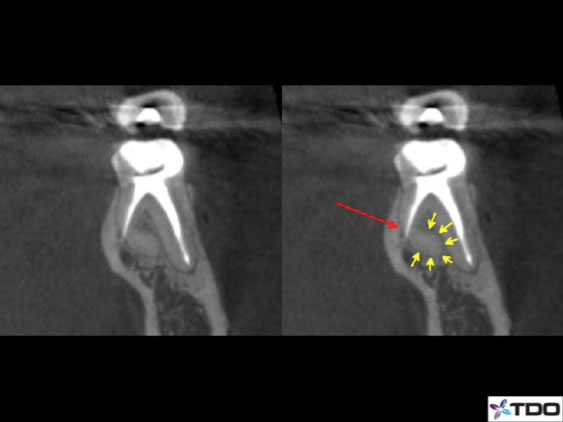

Figure 3: This is a coronal slice view of the DL canal of a lower molar with severe curvature towards the buccal. A perforation is detected at the elbow of the curvature.